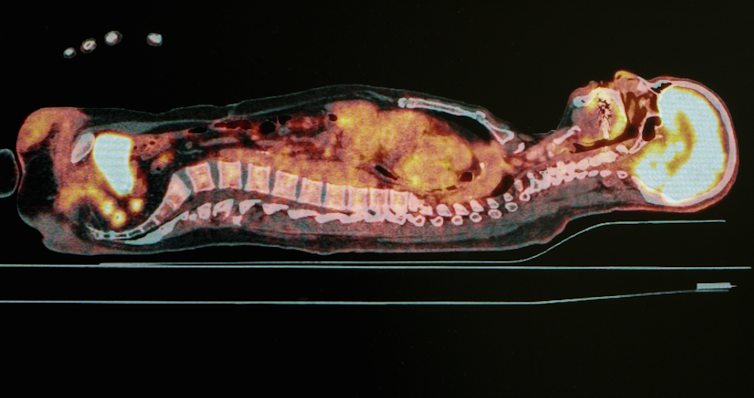

Positron emission tomography (PET)

The imaging techniques used with x-rays, CT and MRI, are mostly designed to observe structural information – this includes the arrangement of anatomy and the location of disease or injuries. PET imaging is a unique imaging process, as it can identify and image functional information such as metabolic (the converting of energy) or chemical processes of internal body organs.

To do this, radioactive substances need to be injected into patients and these are chemically bonded to compounds used by our organs (such as glucose) or molecules that bind to specific receptors or specific types of cells (such as proteins).

These radioactive substances emit gamma rays (another form of ionizing radiation). From their location within the body, the gamma rays pass through tissue and exit the body where they are detected by a PET scanner containing a gamma camera while the patient is lying still.

The PET scanner detects the gamma rays, converts their intensity or strength into an electrical signal and then reconstructs an image based on this intensity. The detectors are arranged around a patient’s body so the originating location of the gamma rays within the patient can be calculated using mathematical processes.

PET imaging is excellent for identifying the activity of tumours within organs that cannot be structurally identified with other imaging techniques.

Even though the thought of being injected with radioactive material may sound dangerous, it actually isn’t. Imaging techniques similar to this have been around for many decades and PET imaging techniques are performed nearly everyday in major hospitals across Australia.